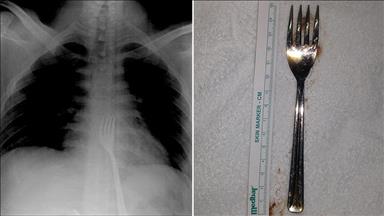

Mide ağrısı şikayetiyle Yüzüncü Yıl Üniversitesi (YYÜ) Dursun Odabaş Tıp Merkezi'ne başvuran Erhan Ö'nün kol saati yuttuğu tespit edildi. Psikolojik rahatsızlığı bulunan Erhan Ö'nün midesindeki saat, kapalı ameliyatla (laparoskopi) çıkarıldı.

Operasyonu gerçekleştiren Dr. Ümit Haluk İliklerden, yaptığı açıklamada, hastanın psikolojik sorunları nedeniyle daha önceden de yuttuğu yabancı cisimlerin ameliyat edilerek yemek borusundan alındığını belirtti.

Gencin yuttuğu 6 santimetrelik kol saatini, tıp literatürüne geçecek bir uygulamayla ameliyat etmeden mideden çıkardıklarını ifade eden İliklerden, şöyle konuştu:

"Şizoaffektif bozukluk tanısıyla hastaneye getirilen gencin tetkiklerinde, yemek borusunda çeşitli cisimlerin olduğu tespit edildi. Bu cisimler yapılan başarılı ameliyatla yemek borusundan alındı. Ancak hastanın rahatsızlığının devam etmesi üzerine yaptığımız tetkiklerde, gencin midesinde saat olduğunu tespit ettik. Bunun için operasyon yapılması gerekiyordu. Ameliyat yapmayı düşündüğümüzde Prof. Dr. Çetin Kotan hocamızın midedeki saatin çıkarılması için bize ilettiği operasyon şekli üzerinde yoğunlaştık. Endoskopi yönteminin ağır geçeceğini göz önünde bulundurduk. Prof. Dr. Remzi Kızıltan eşliğinde laparoskopik yöntem dediğimiz kapalı ameliyatla saati mideden çıkarttık."

Midedeki saatin çıkarılması için gerçekleştirilen operasyonu anlatan İliklerden, mideye takılan portun yerinden çıkartılarak düşük basınçla şişirildiğini ve mideye optik kamera gönderildiğini ve bunun çok bir özel teknik olduğunu söyledi.

"Saat normal yapılan ameliyatla da çıkarılırdı. Ama daha büyük bir ameliyatla mide açığa çıkarılarak yaklaşık 10 santimetre kesilecekti. Ancak hastanın genç olduğunu ve yara yeriyle birçok sıkıntı çekebileceğini düşündük. Hocamızın sayesinde portlardan birkaç santimetrelik kesiklerle dışarıdan aletler kullanılarak operasyonu yaptık. Mide port yerinden dışarı şekilde düşük bir basınçla şişirildikten sonra, optik kameramızda görülen saat yandan sokulan aletle dışarı çekildi. Çok başarılı bir ameliyatla çıkardık."